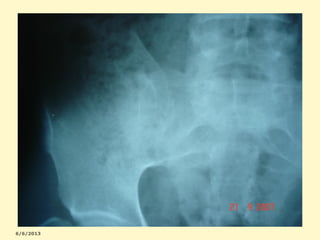

Graduação radiológica da SI

0=normal

3=sacroileite moderada

1=suspeita

4=anquilose óssea

2=sacroileite mínima

Esclerose marginal bilateral

ESCLEROSE + ALARGAMENTO +IRREGULARIDADE

A-PSEUDODILATAÇÃO E LESÃO ESCLERÓTICA

B-FUSÃO DAS SACROILÍACAS

Acometimento unilateral de sacroilíaca